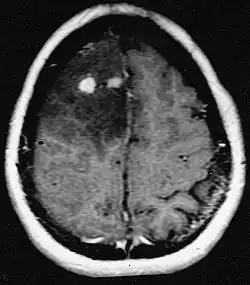

![]() Glioblastoma arising in an astrocytoma. This spinal cord exhibits both a lightly staining microcystic astrocytoma as well as a darkly staining glioblastoma.  | |